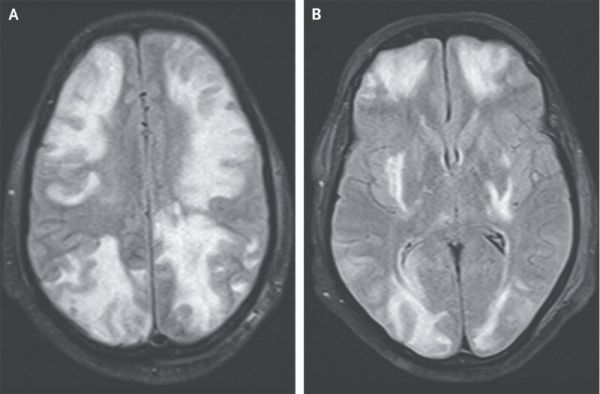

头部 T2 加权 MRI :皮质和皮质下白质出现血管源性水肿,信号强度较高(图 A 图 B 为不同轴向水平表现)

MRI 显示皮质和皮质下白质血管源性水肿,信号强度较高,MRI 表现与 PRES 相符,该病常与肾脏疾病和高血压相关。

患者有 IgA 肾病病史,首先考虑是否药物副作用。患者 2 周前开始接受环孢菌素治疗,可能引起「可逆性后部脑病综合征 (PRES)」,表现为血管源性水肿,符合 MRI 结果。

且停用环孢素一周后,患者症状和 MRI 异常基本消失如图,可以确诊为 PRES。

需要说明一下,PRES 虽然病名里带「后部」,主要在大脑后循环区域有典型影像学表现,也可能累及大脑皮层。

3、影像学:颅内多灶性、累及顶枕叶为主,在 T2WI 或 FLAIR 高信号,DWI 血管源性水肿;